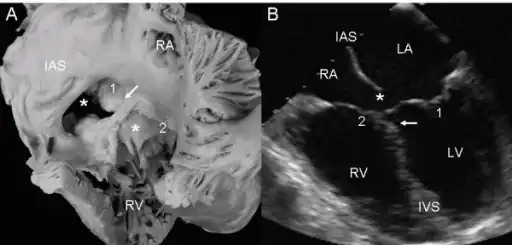

- a,b)Atrioventricular septal defect with two separate atrioventricular valves.

- Ultrasound showing a complete atrioventricular septal defect